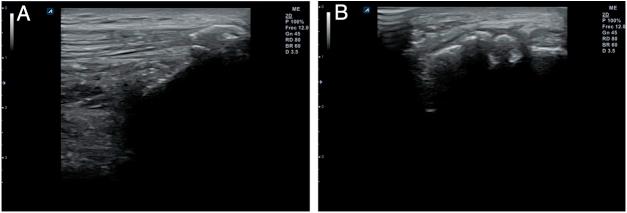

Musculoskeletal ultrasound (MSU) is a technique which has been extended to practically all medical specialties that comprise this pathology. Family Doctor (FD) has not been away from this process due to its great wide of competences, using it in different scenarios inside his common practice in which he can get profits in a reliable, efficient and effective way. Ultrasound equipment incorporation in Primary Care (PC) centers is an increasing reality, contributing to high ranges of accessibility, immediacy and clinic handle capability, and thus, together with the high prevalence in this area in locomotor apparatus, turns MSU into an strategic action for the improvement of the resolving capacity and consequently for the health care. To ensure proficiency among users, it's being necessary to define the benefits and potential risks its use can cause, as well as its different scenarios, avoiding unnecessary explorations and optimizing the investment of this resource at PC level. This paper pretends to summarize the state of the art of the musculoskeletal ultrasound and its benefits for the FD into this efficient and effective scenarios.

肌肉骨骼超声(MSU)是一种已被应用于几乎所有涉及该病理学的医学专业的技术。家庭医生(FD)因其广泛的能力范围也参与到了这一进程中,在其日常诊疗的不同场景中使用该技术,从而能够以可靠、高效且有效的方式从中获益。超声设备在基层医疗(PC)中心的应用日益普遍,这有助于提高可及性、即时性和临床处理能力,因此,鉴于运动系统在该领域的高患病率,肌肉骨骼超声成为提高诊断能力进而改善医疗保健的一项战略举措。为确保使用者的专业水平,有必要明确其使用可能带来的益处和潜在风险,以及不同的应用场景,避免不必要的检查,并在基层医疗层面优化该资源的投入。本文旨在总结肌肉骨骼超声的现状及其在这些高效有效场景中为家庭医生带来的益处。